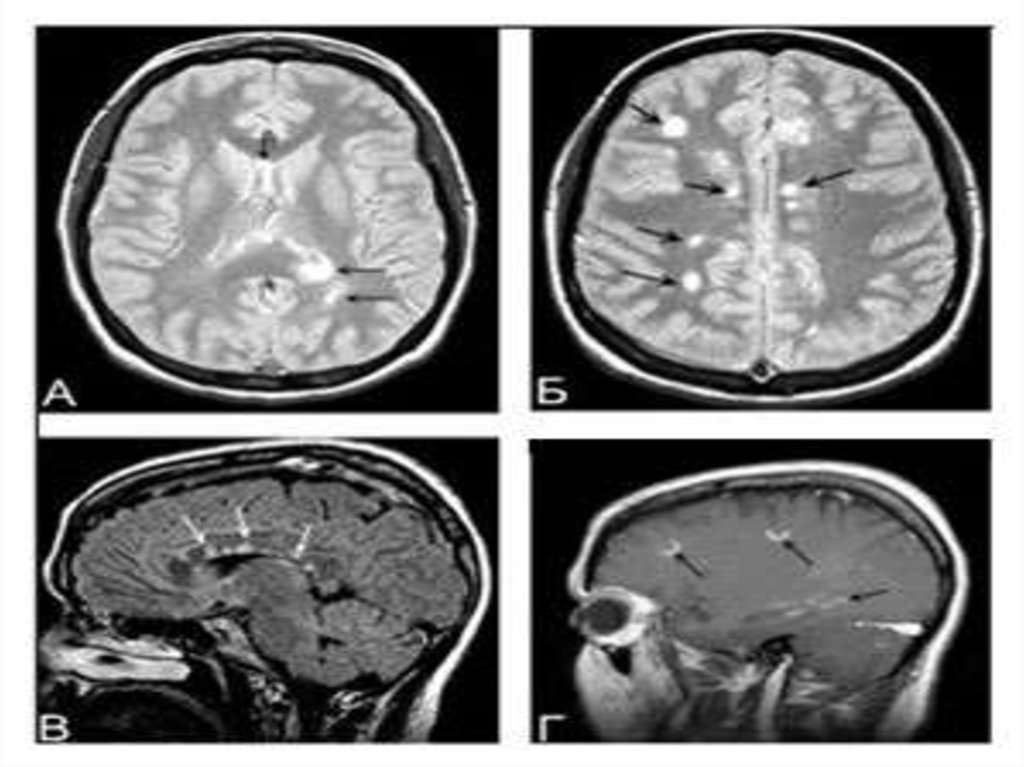

Рассеянный склероз (РС) – хроническое, прогрессирующее

заболевание центральной нервной системы,

патоморфологическую основу которого составляют

процессы демиелинизации нервных проводников

(распад миелиновой оболочки) в головном и спинном

мозге. Клинически РС характеризуется рассеянной

неврологической симптоматикой, слагающейся из

преимущественного поражения оптической,

пирамидной и мозжечковой систем головного и

спинного мозга. В большинстве случаев, особенно на

начальной стадии, течение заболевания

ремиттирующее с последующим переходом в медленнопрогредиентное. Дебютирует РС в молодом возрасте

(20-40 лет), однако не исключается возникновение

заболевания у детей и лиц старше 50 лет.